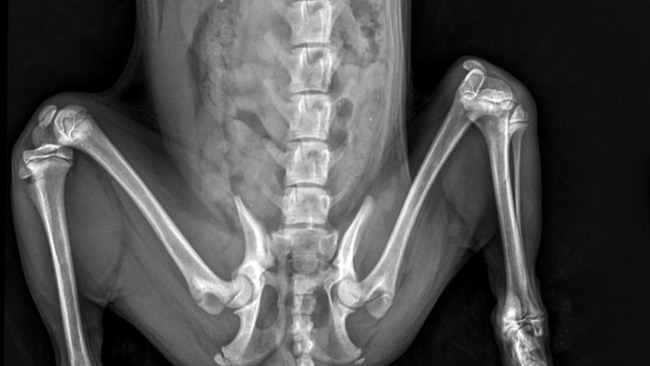

Zostałam zabrana od niedobrego Pana, który trzymał mnie w klatce i nie traktował dobrze. Urodziłam się z przesunięta rzepką, a poprzez nie odpowiednie traktowanie mnie doprowadziła do atrofii mięśni mojej łapki co spowodowało dysplazje moich bioderek.